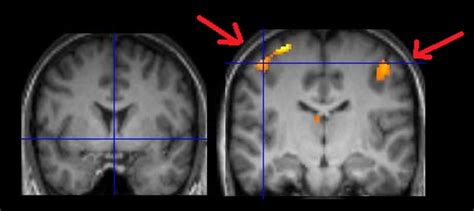

Il neuroimaging rappresenta una risorsa indispensabile nelle neuroscienze cognitive, comprendendo un ventaglio di tecniche che permettono di visualizzare la struttura e la funzione del cervello. Tra le metodologie più diffuse troviamo la Risonanza Magnetica Funzionale (fMRI) e la Tomografia a Emissione di Positroni (PET). Questi strumenti consentono ai ricercatori di osservare quali aree del cervello diventano attive durante l'esecuzione di specifici compiti cognitivi, fornendo mappe dettagliate dell'attività neurale.

La fMRI, in particolare, misura i cambiamenti associati al flusso sanguigno nel cervello, un indicatore indiretto dell'attività neuronale. Questa tecnica offre una risoluzione spaziale eccellente, permettendo di identificare con precisione le regioni cerebrali coinvolte in un dato processo cognitivo. La PET, d'altra parte, utilizza traccianti radioattivi per misurare processi metabolici a livello cerebrale, rivelandosi utile nello studio di malattie neurodegenerative e disturbi cognitivi, nonché per comprendere l'effetto di farmaci sul cervello.

I metodi di neuroimmagine strutturale e funzionale forniscono un supporto inestimabile alle neuroscienze cognitive e trovano applicazione pratica in ambito neuropsicologico e psicologico clinico. La progettazione e l'analisi di esperimenti che utilizzano tecniche di neuroimaging, come la Risonanza Magnetica Strutturale (sMRI) e la Risonanza Magnetica Funzionale (fMRI), richiedono un insieme di conoscenze pratiche di base. I corsi di laboratorio dedicati a queste tecniche guidano gli studenti attraverso le procedure di processamento e analisi dei dati che godono del maggior consenso nella comunità scientifica. Le applicazioni pratiche spaziano dalle neuroscienze cognitive alla neuropsicologia e alla psicologia clinica, dimostrando la versatilità e l'importanza di queste metodologie.